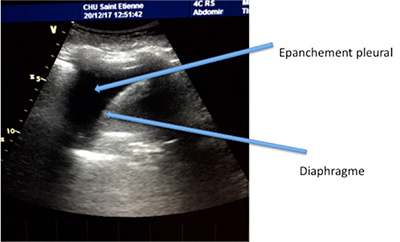

Grâce aux ultrasons, l’exploration de la plèvre se fait sans irradiation ni geste invasif. On peut déceler les pneumothorax (air dans la plèvre), les pleurésies (liquide dans la plèvre) (photo 11) ou repérer une masse ou un nodule pulmonaire au contact de la plèvre (photo 12)